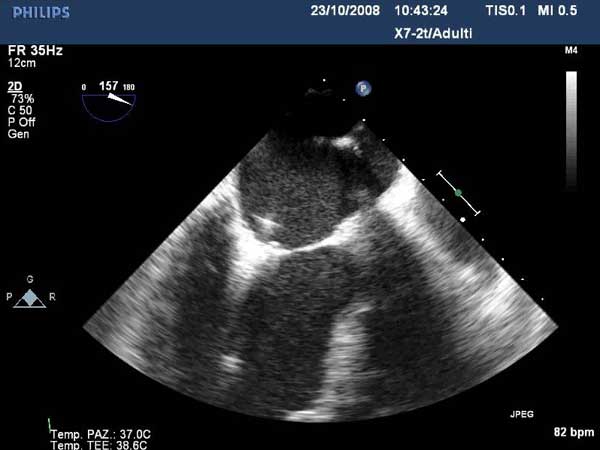

In absence of controlled clinical trial data which are forthcoming from the EVEREST II randomized study, the indications for the MitraClip therapy are currently based on registry experience and will evolve as the technique improves, experience is growing and the data to demonstrate efficacy and safety becomes available. At this time, the best indication for the MitraClip therapy is for symptomatic patients with clinically significant functional or degenerative MR who are at high or increased risk for open heart surgery. From a pure technical standpoint, the procedure so far has only been demonstrated in a subgroup of patients with specific anatomical characteristics which are summarized below and shown in Figure 3. Anatomic suitability is assessed by transesophageal echocardiography, and mitral regurgitation should originate from the central portion of the valve involving the A2-P2 segments, since the device is not ideal to work in the commissures at this time; the mechanism of MR can be either a prolapse/flail or MR due to restricted leaflet motion unrelated to rheumatic disease; the separation between the two leaflets at the site of regurgitation should be limited; severe annular dilatation and/or severe calcification should be absent or is relevant. In case of flail, the flail segment width should be less than 15 mm, and the flail gap less than 10 mm. Figure 4 is a 3D echo image of a patient with posterior leaflet prolapse selected for MitraClip therapy. In case of functional MR, the leaflets should have a minimal residual tissue available for coaptation with the MitraClip device. Figure 5 shows 2D color Doppler jet extension over the coaptation line at TEE short axis transgastric view, while Figure 6 shows the tenting area and the coaptation depth of a patient undergoing MitraClip implant.

1. Quality of the grasp, valve function and adequacy of repair (reduction of MR) are assessed using echocardiography and fluoroscopy if desired (Figures 16-18). The clip is closed further as needed under real time MR assessment.